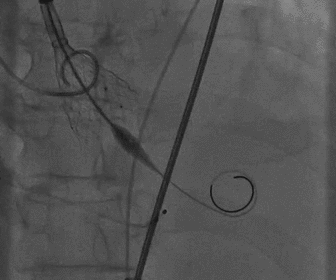

根部造影

球囊预扩

胶囊腔定位

瓣膜释放

造影观察瓣膜形态